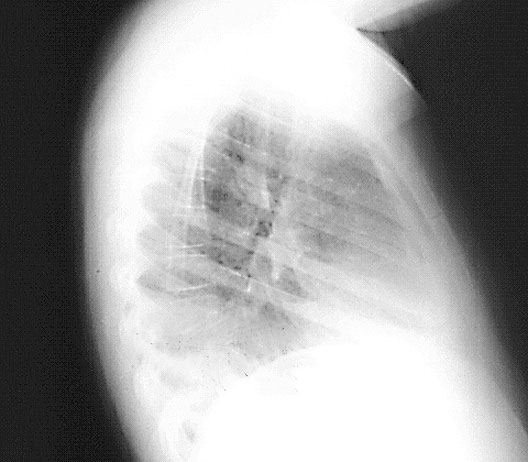

Lateral Chest X-Ray

*Arrows point to diaphragm